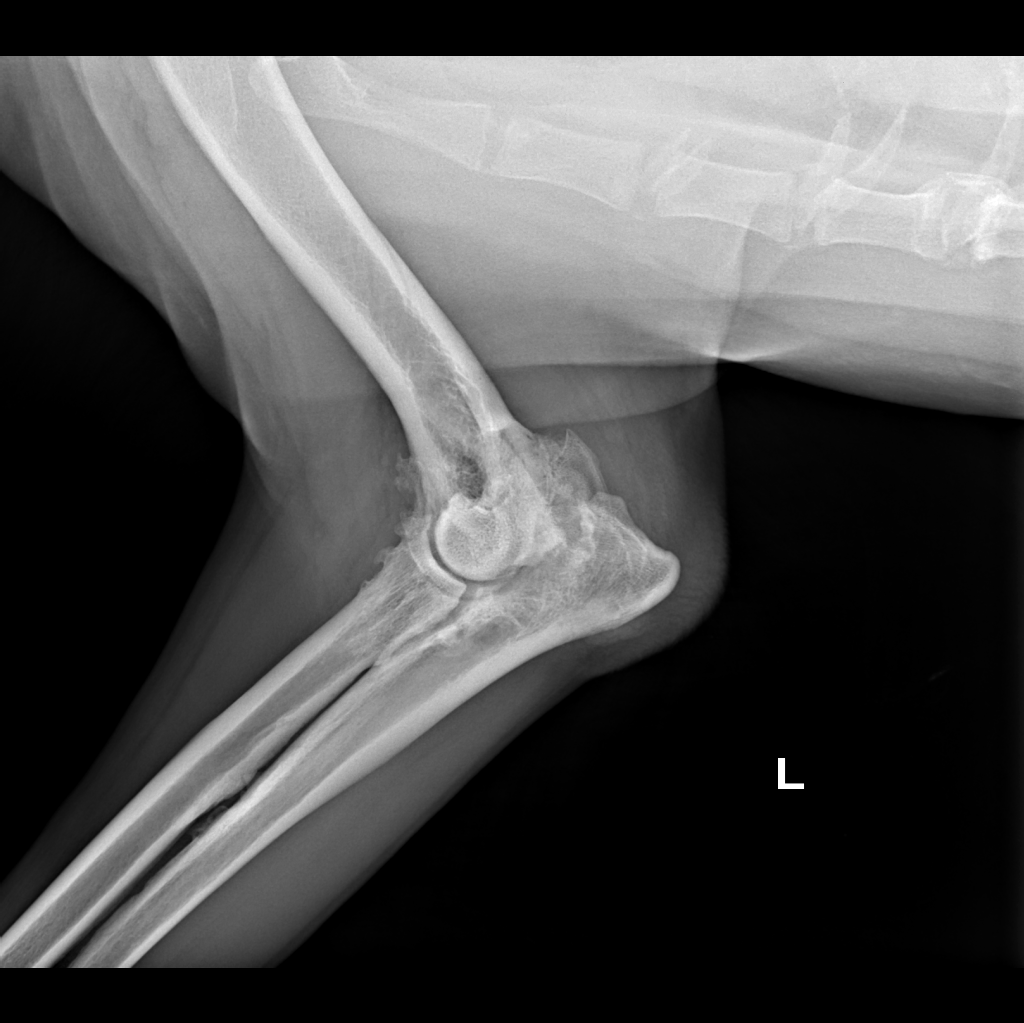

Elbow Dysplasia in a Golden Retriever

Male, 12 yo, 32 kg, golden retriever

presented with chronic 3 grade left forelimb lameness

Orthopedic examination reveals pain response during spine palpation and reduced ROM in flexion and extension of left elbow.

x-ray with awake patient was performed on forelimb (medio-lateral view of elbows and dorso-palmar view of carpus) and latero-lateral view of thoracic and lumbar vertebrae.

Radiographic findings consisted of severe left elbow dysplasia, in addition to spondylarthrosis (thoracic vertebrae and thoraco-lumbar region)